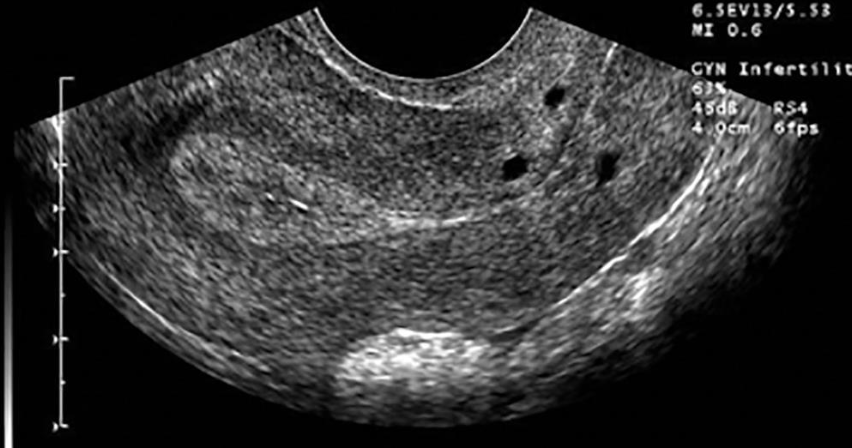

– Two partially or completely separate endometrium form.

– The uterus is normally shaped

– Most common congenital uterine anomaly causing infertility.

Septate Uterus